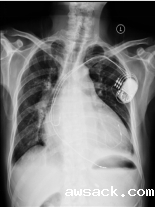

人工心脏起搏器植入术 ICD(植入式除颤复律仪) CRT(心脏再同步治疗)

人工心脏起搏器植入术:用特定频率的脉冲电流,经过导线和电极刺激心脏,代替心脏的起搏点带动心脏搏动的治疗方法,主要治疗重症慢性心律失常。